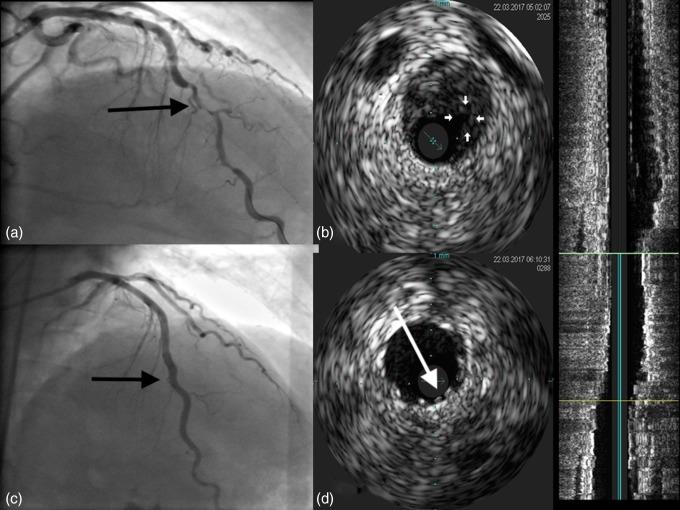

A 55-year-old man without any cardiac history has been admitted to Ist Department of Cardiology due to anterior wall infarction. In echocardiography (ECG), local anterior wall dysfunction has been observed, with good left ventricle ejection fraction. In angiography performed immediately after transfer to hospital, long lesion in left anterior descending coronary artery has been visualized with high angiographic suspicion of dissection and intramural coronary hematoma. Intravascular ultrasound (IVUS) has been performed and further confirmed the diagnosis of hematoma - LAD was stented using three coronary stents. IVUS has confirmed good position of stents. Integrillin has been used. Periprocedural time was uncomplicated. ECG showed resolution of myocardial infarction pattern and evolution of infarction has been observed. The patient was discharged home in good clinical condition. Coronary dissection and coronary hematoma are the potential cause of infarction and IVUS, despite optical coherence tomography being reference nowadays, is still a very valuable tool in diagnosis and treatment guiding in such cases.